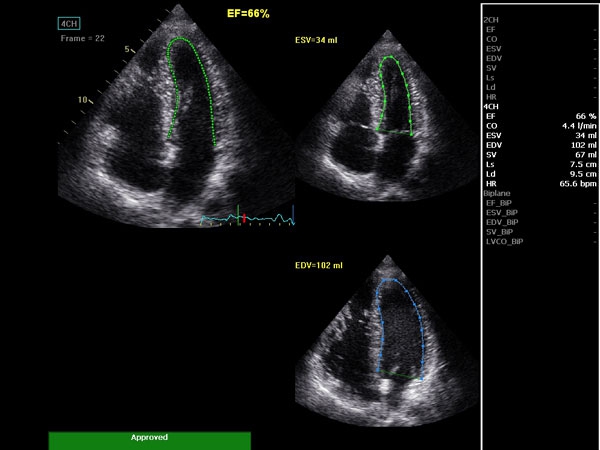

• AutoEF (Auto Ejection Fraction) — функция автоматической недоплеровской количественной оценки глобальной сократительной функции левого желудочка с выделением зоны интереса по технологии спекл-трекинга.

• AFI (Automated Function Imaging) — автоматическое отображение функции ЛЖ — функция позволяет производить качественную и количественную недоплеровскую оценку региональной сократительной функции левого желудочка.

AUTO 2D EF:

Да

• 2D Auto EF